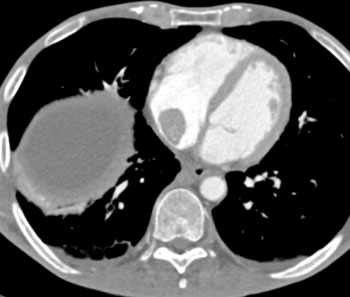

![]() | Question 7: 50ish year old male with increasing chest and abdominal discomfort. What is the most likely diagnosis in this case? |